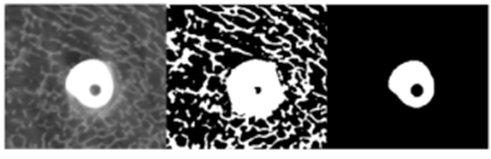

Beyond conventional implants, micro-CT plays a central role in evaluating bone grafts, bioactive coatings, and tissue engineering scaffolds. Porosity, pore size distribution, and interconnectivity can be quantified in three dimensions, enabling correlation with vascularization, bone ingrowth, and mechanical performance. Because these structures are often heterogeneous, volumetric imaging is essential for meaningful characterization.

Porosity is a defining structural property of scaffold implants because it determines the volume fraction of void space available for tissue ingrowth, vascularization, and nutrient transport. Micro-CT analysis shows that total porosity alone is insufficient to predict biological performance; instead, the spatial distribution of solid material and voids must be quantified in three dimensions to ensure repeatable and biologically relevant measurements.

High porosity increases surface area and space for calcified or soft-tissue infiltration, but if pore dimensions approach the voxel size or are poorly resolved, segmentation accuracy and derived metrics become unreliable. Consequently, high-resolution micro-CT imaging is essential to minimize partial-volume effects and enable robust quantification of scaffold architecture, including thickness and separation of structural elements.

Equally important is pore interconnectivity, which governs scaffold permeability and determines whether internal pore spaces are accessible to cells, fluids, and vasculature. Most biological scaffolds do not contain isolated, discrete pores; instead, they form a highly interconnected pore network in which nearly all internal space is theoretically connected to the exterior in three dimensions.

Micro-CT–based analyses therefore focus on characterizing accessibility of this interconnected pore space using virtual object or “virtual sphere” methods, which assess the maximum pore size through which cells could realistically migrate. These analyses demonstrate that although overall interconnectivity may exceed 98%, functional permeability decreases sharply as the required passage diameter increases, linking scaffold architecture directly to biological feasibility of cell ingrowth and tissue regeneration.